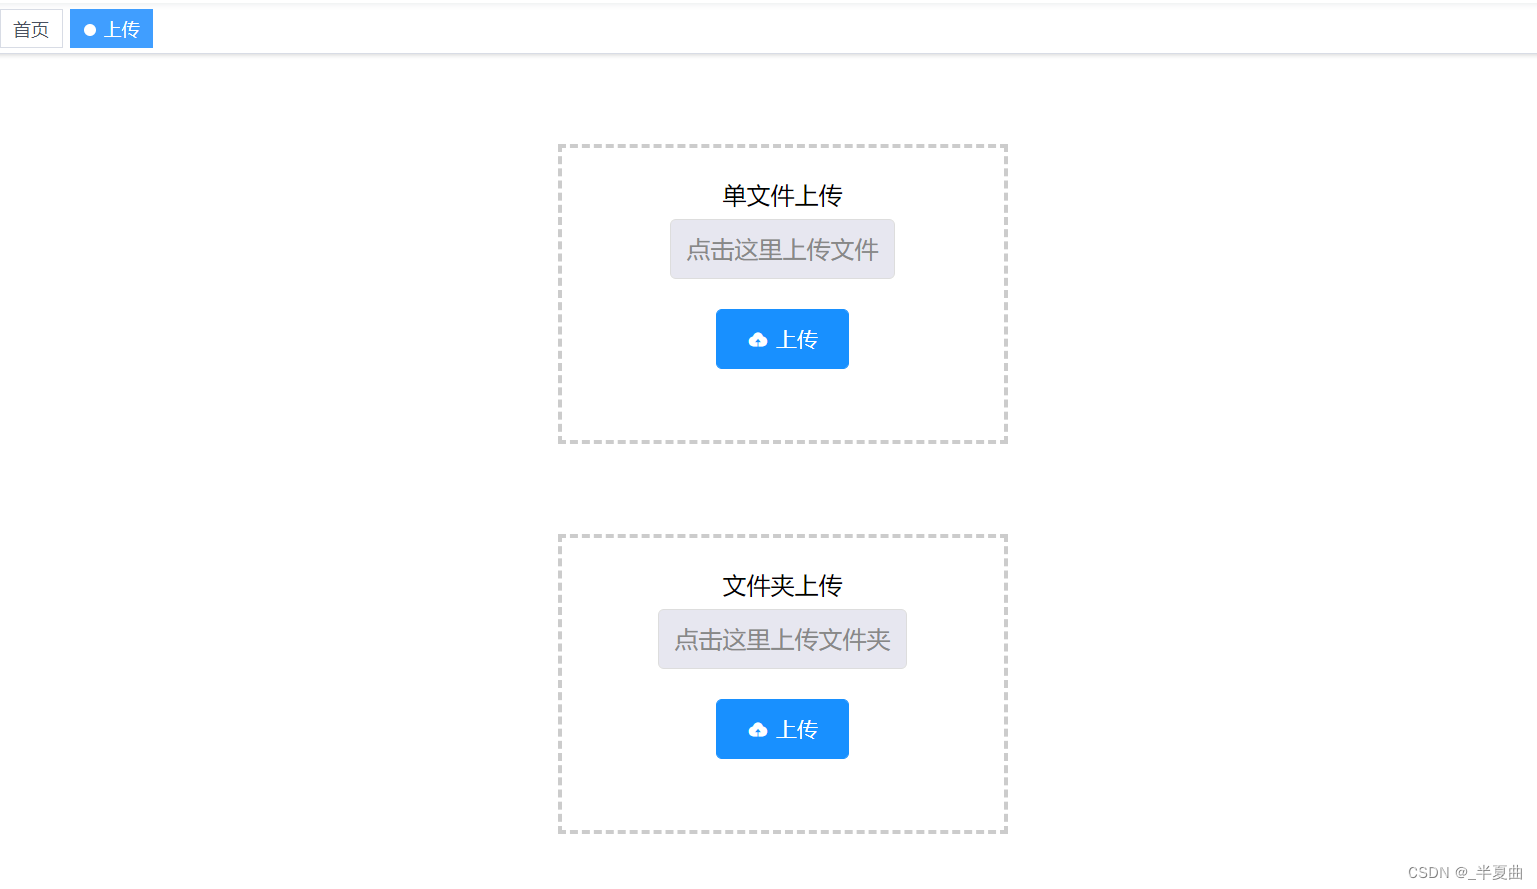

手动上传Dicom文件/文件夹,及接收Dicom服务器的Dicom文件集功能;

手动上传Dicom文件/文件: